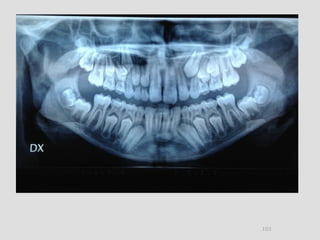

Panoramic (reconstructed from CT)

The most likely diagnosis for the facial asymmetry of this young girl is an

undiagnosed condylar fracture that most likely happen when she falled on a meta

crossbar bar ladder 2 or 3 years ago while she was 4 - 5 years old or so. The

condylar stump has healed and a new condylar head has formed, but the losted

substance of the condyle is gone. Therfore, the height of the ramus has

shortened.

The left ramus and condylar neck are shorter and the left eminence has no slope

if any. Healing and normal growth had reshaped both condyle and eminence.

!

Read more

When looking to the condyle from an anterior view, one can see the oblong

shape of a condyle but the left condyle is smaller.

The midline are not coincident. Note that the lower midline is toward right like

the occlusal plane canting to the right. This can be explained by the lack of

heigh of the left ramus and as normal growth occur, there is a wagon wheel

effect and the midline deviate toward the normal side, the occlusal plane is

moving up on the affected side.